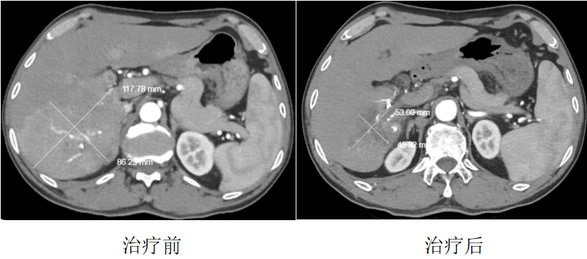

让人欣慰的是,聂先生坚持了下来。2026年1月,他复查时做了增强CT,结果让人惊喜:肝脏里原本活跃的肿瘤已经基本“灭活”,原来堵塞血管的癌栓也明显缩小了。同时,他的甲胎蛋白指标大幅下降,意味着肿瘤被控制得很好。无论是从影像上看,还是从血液指标看,疗效都非常显著。